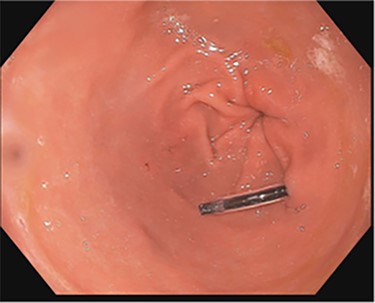

Side-by-side comparison of foreign body perforating through stomach (right) and sealed site of perforation after endoscopic removal (left).